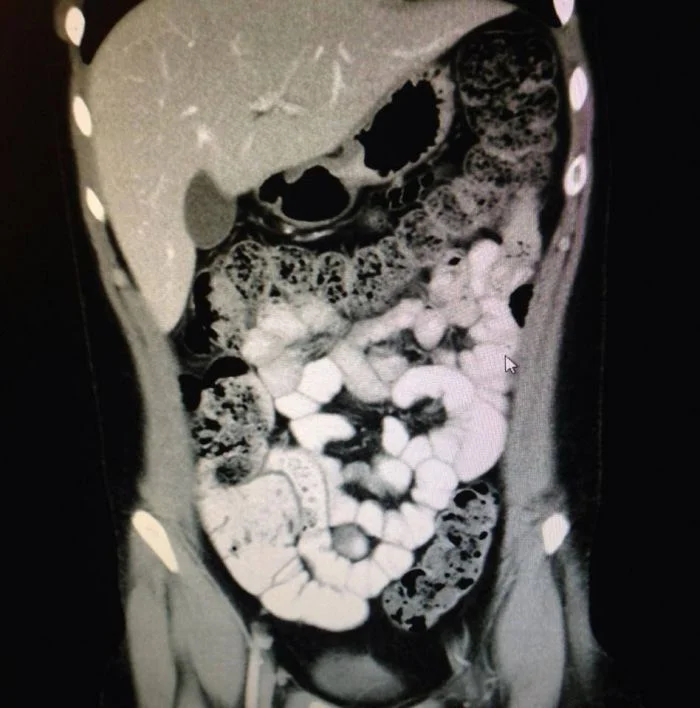

18. Давний запор на рентгеновском снимке